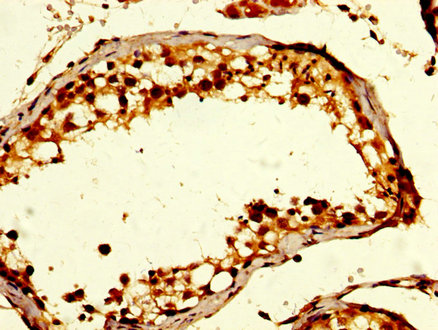

IHC image of CSB-PA009343LA01HU diluted at 1:200 and staining in paraffin-embedded human prostate tissue performed on a Leica BondTM system. After dewaxing and hydration, antigen retrieval was mediated by high pressure in a citrate buffer (pH 6.0). Section was blocked with 10% normal goat serum 30min at RT. Then primary antibody (1% BSA) was incubated at 4°C overnight. The primary is detected by a biotinylated secondary antibody and visualized using an HRP conjugated SP system.